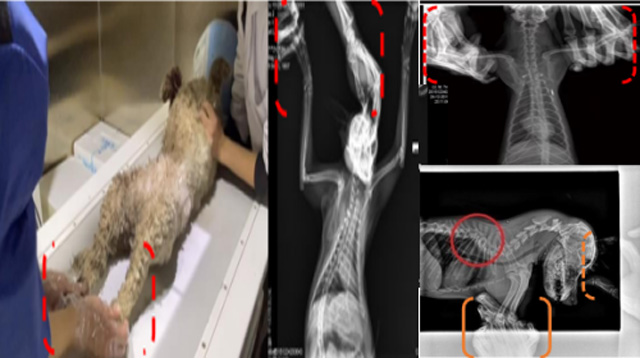

現(xiàn)在寵物醫(yī)療設(shè)備得到高速發(fā)展,現(xiàn)在有越來越多的寵物診療機構(gòu)配置X射線裝置如寵物DR。寵物骨折或者有其他疾病不能通過直觀看出來的。寵物診所醫(yī)生都會使用寵物DR來做輔助檢查。但是有時候?qū)櫸镝t(yī)生沒有加強防護,就在寵物DR室給寵物拍X片做檢查。這樣也是會受到X射線的輻射。因為X射線上崗是屬于職業(yè)病危害崗位。長期的輻射會對人體造成一定的危害。寵物醫(yī)生也需要接受X射線照射的上崗前都必須進行放射工作人員的職業(yè)健康體檢。體檢不合格的話是不能擔任放射工作的。未經(jīng)上崗前職業(yè)健康體檢的勞動者從事接觸職業(yè)病危害作業(yè)的行為,已經(jīng)違反了《中華人民共和國職業(yè)病防治法》第三十五條規(guī)定,依據(jù)《中華人民共和國職業(yè)病防治法》第七十五條規(guī)定,需要進行整改罰款。開展寵物放射診療活動,在日常工作中,對本機構(gòu)的X射線危害的職業(yè)病防治,需要知道并做到以下內(nèi)容:

建造X射線機房時尋找專業(yè)防護施工隊伍,對機房四方及上下方墻體進行屏蔽防護,盡可能隔室操作,使用鉛防護門并安裝工作指示燈張貼警示標識進行提醒。放射工作人員跟寵物主進入DR室需要穿戴鉛衣、鉛帽、鉛手套等做好防護,減少X射線的輻射。避免暴露在照射范圍中。寵物醫(yī)生上崗前、在崗時、離開崗位時候的職業(yè)健康體檢。如果檢查異常就需要復(fù)查跟調(diào)離放射崗位。實施個人劑量監(jiān)測和防護知識培訓(xùn)。并在勞動合同中向放射工作人員告知X射線危害相關(guān)內(nèi)容。定期委托職業(yè)技術(shù)服務(wù)機構(gòu)對機房防護、放射診療設(shè)備性能進行檢測。不能忽略了對人的保護。